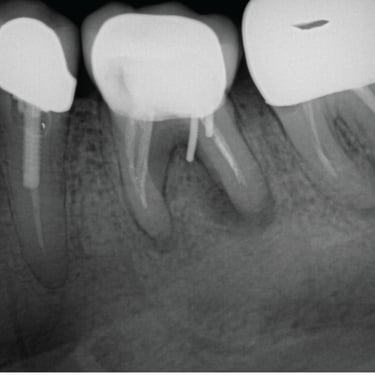

Hipercementosis

La hipercementosis es un engrosamiento anormal del cemento radicular del diente, a menudo debido a una inflamación crónica o trauma.

Los pacientes generalmente no tienen síntomas, pero la condición puede ser descubierta en una radiografía.

El tratamiento no suele ser necesario a menos que cause problemas con la extracción del diente.